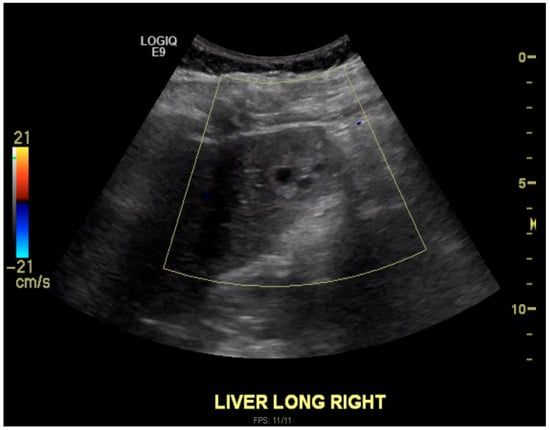

Ruptured Heterotopic Pregnancy: Laparoscopic Management, Preserving Intrauterine Viability

Pregnancy (HP), defined as the coexistence of intrauterine and ectopic gestations, is a rare condition, especially in spontaneous conception, but it is a life-threatening obstetric emergency when rupture occurs, with a reported maternal mortality rate of 0.03%. Diagnosis is often delayed because confirmation of an intrauterine pregnancy can mask clinical signs of a concurrent ectopic gestation. Early recognition and prompt surgical intervention are therefore critical to maternal safety and preservation of intrauterine viability. This case highlights the diagnostic challenges and successful management of a spontaneous ruptured heterotopic pregnancy. Case presentation: A 34-year-old Middle Eastern woman, gravida 4, with a spontaneous conception, presented with sudden severe lower abdominal pain and signs of acute hemoperitoneum (hypotension, tachycardia, and marked peritoneal signs). Transvaginal ultrasound demonstrated a viable intrauterine pregnancy at 9 weeks 4 days gestation, together with a ruptured left tubal ectopic pregnancy of similar gestational age. The patient underwent urgent laparoscopic left salpingectomy with evacuation of approximately 1200 mL of intraperitoneal blood and clots. Postoperatively, she developed significant anemia (hemoglobin drop from 11.2 g/dL on admission to 6.5 g/dL) requiring transfusion of four units of packed red blood cells. Serial ultrasonographic follow-up confirmed ongoing viability of the intrauterine pregnancy, which ultimately resulted in a live birth at term. Progressive resolution of the postoperative pelvic hematoma was also noted. Conclusions: Ruptured heterotopic pregnancy remains a diagnostic and therapeutic challenge. This case, along with a synthesis of the contemporary literature, demonstrates that a high clinical index of suspicion, timely ultrasound diagnosis, and immediate minimally invasive surgical management are paramount. Furthermore, rigorous postoperative monitoring and resuscitation, including targeted transfusion, are essential to achieve maternal stabilization while allowing continuation of a viable intrauterine pregnancy, with reported live birth rates exceeding 70% following timely intervention. Full article